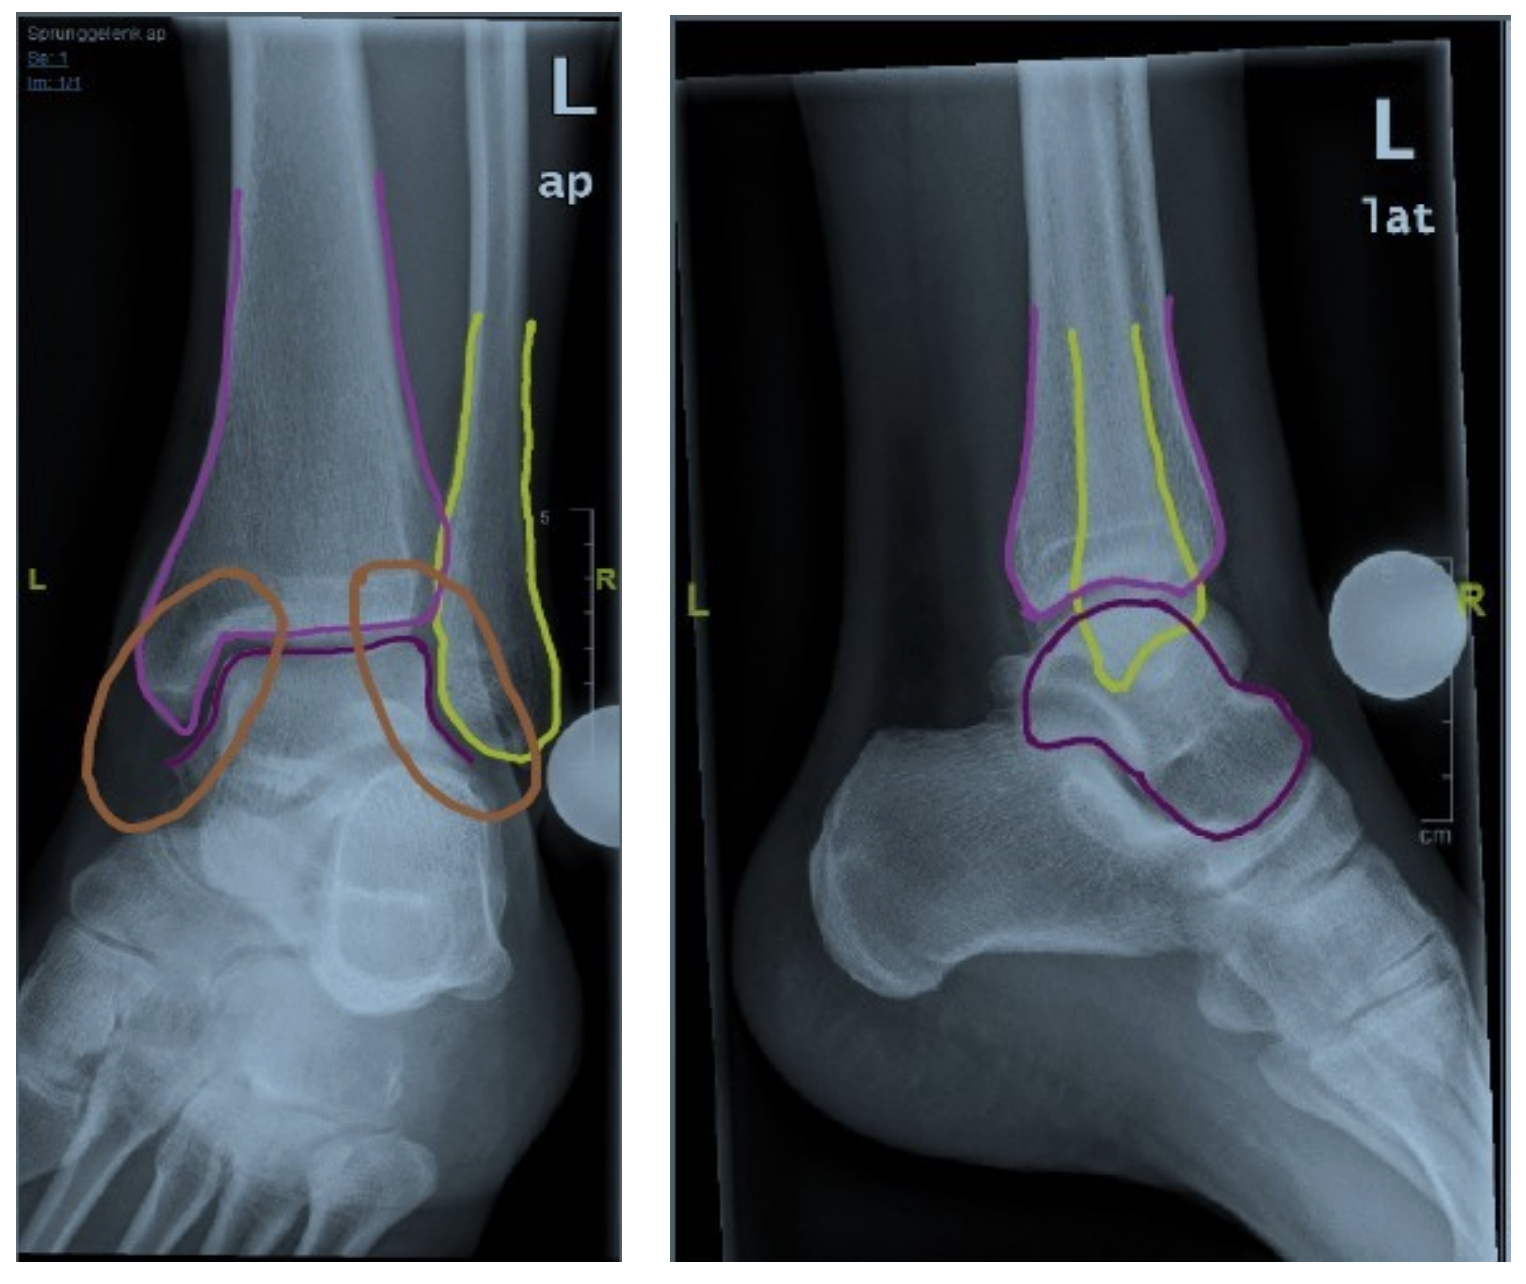

Röntgen OSG Beurteilung

- Umfahren der Fibula (gelb)

- Umfahren der Tibia (pink)

- Umfahren des Talus(lila)

- Check tibio-talarer Abstand

- Check fibulo-talarer Abstand

- abschließender Check der Gelenkkongruenztibio-talar und fibulo-talar

- Umfahren der Fibula

- Umfahren der Tibia

- Umfahren des Talus und Kalkaneus

- Check Gelenkkongruenztibio-talar

- Check Cyma-Linie (Chopard-Gelenks-linie)